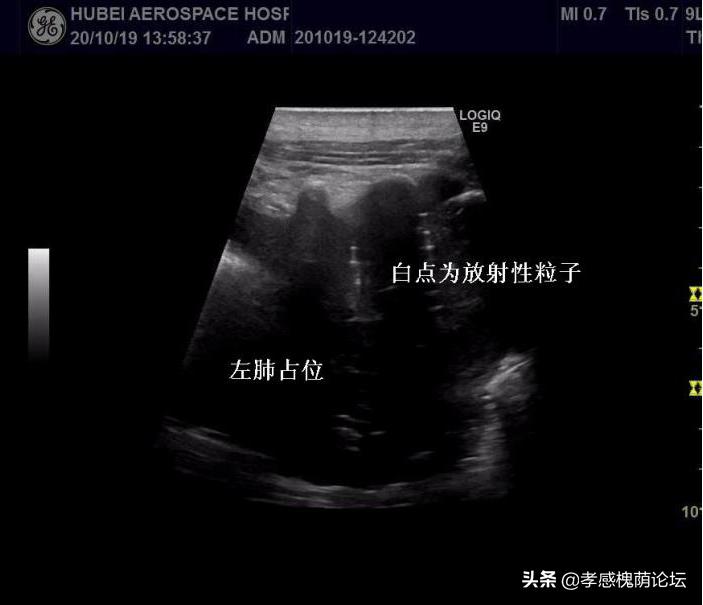

术前,使用放射性粒子植入治疗计划系统,对治疗过程中涉及到的穿刺方法、布针、粒子植入数量及排布进行周密的设计。在局部麻醉下,汪一平、任宏义等医师借助超声引导,将粒子按照术前方案植入瘤体中,手术顺利。术后进行局部敷料包扎,患者无不适。

超声引导下放射性粒子近距离治疗肿瘤技术的应用,是通过超声引导技术,以微创的方式,对肿瘤进行近距离*伤杀**,为失去手术机会的晚期肿瘤、多发转移瘤以及无法承受手术的肿瘤患者提供生存机会,提高患者的生活质量,从多方面弥补了手术及放化疗的不足。